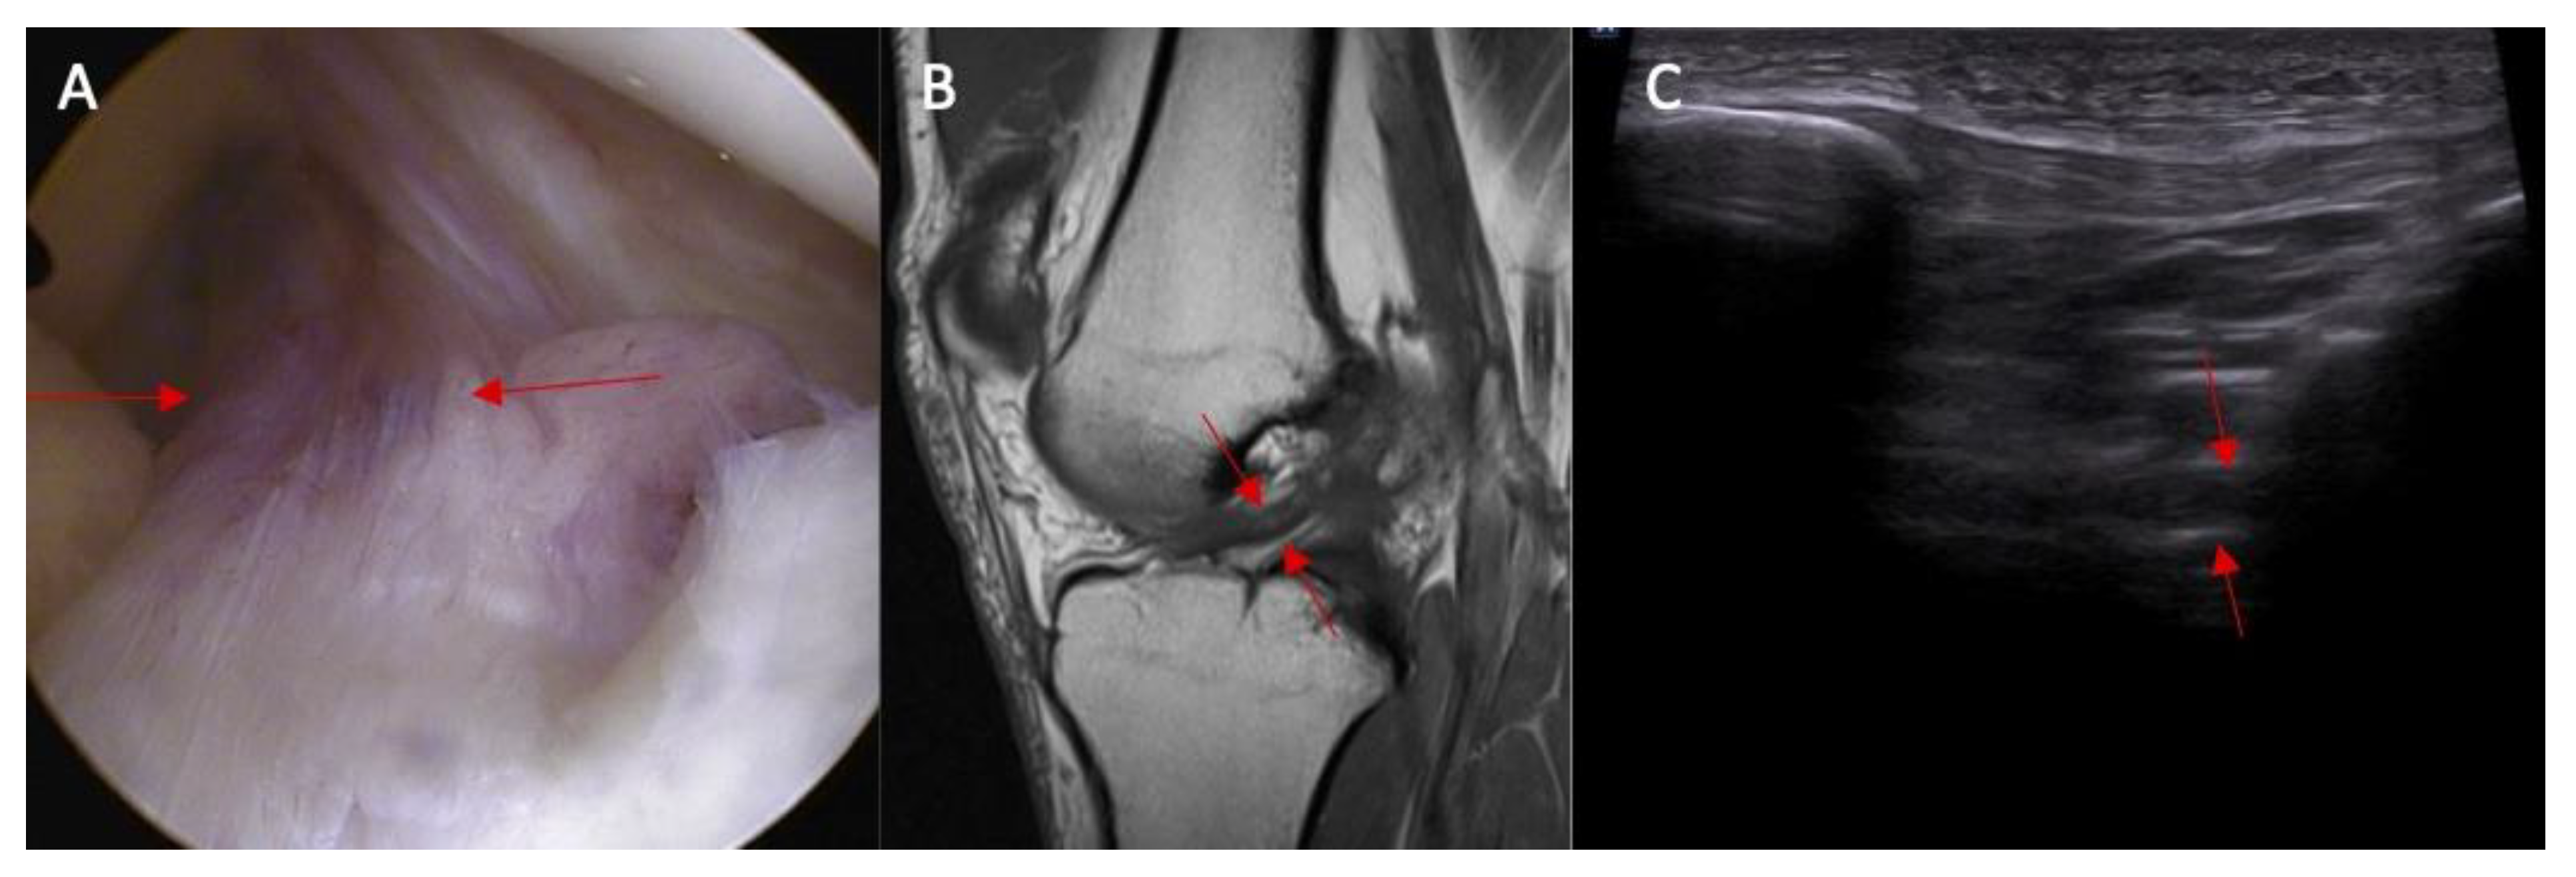

- Swelling/scarifications of the ACL/posterior crucial ligament (PCL) with change of the morphology of the posterior joint capsule complex—the patient is in prone position with knee full extension. The transducer is applied parallel to the long axis of the lower limb.

2.1. Part I—Anatomical Study

3.1. Part I—Anatomical Study